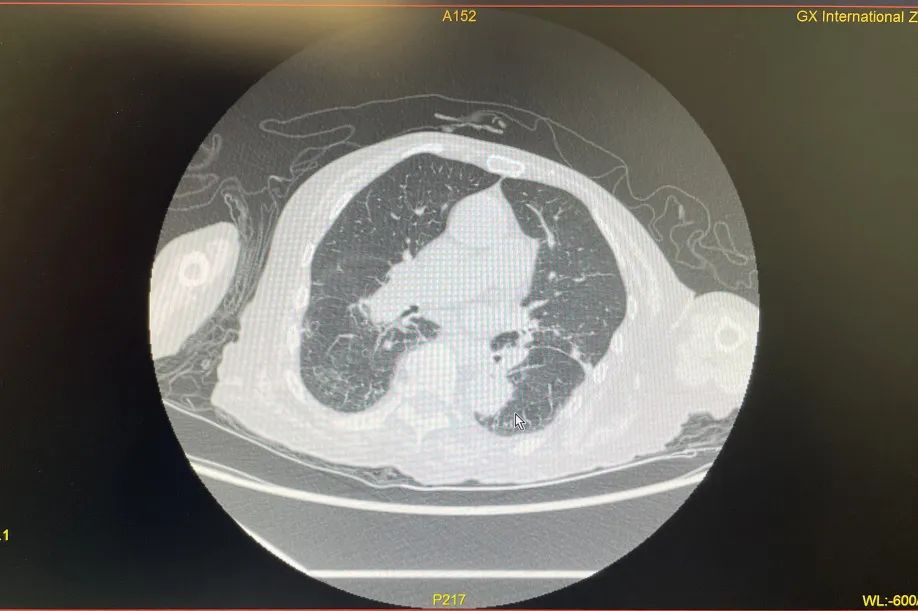

在肾病科团队的持续努力下,胡奶奶消化道出血状况解除;随后肺炎程度减轻,血氧回归正常值,脱离生命危险,气喘、意识不清、烦躁等症状消失,核酸结果转阴,后顺利康复出院。

治疗后,胡奶奶肺炎程度减轻,氧合指数、氧分压改善明显,脱离生命危险